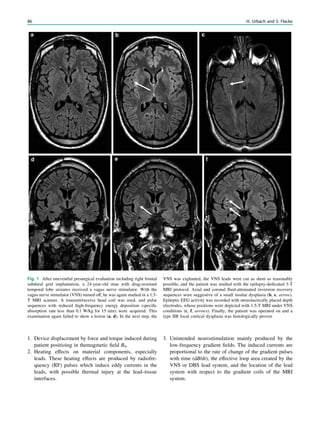

Fig. 2 Dural a. v. fistula. A 53-year-old man presented with two tonic–

clonic seizures. MRI shows circumscribed edema in the left frontal lobe

(a, hollow arrow) and an abnormal vessel running in the left sulcus

rectus (c, arrow). The digital subtraction angiogram of the left internal

carotid artery shows a frontobasal dural arteriovenous fistula fed via

ethmoidal arteries (d, arrow) and confirms the abnormal vessel as a

draining vein (e, arrow)